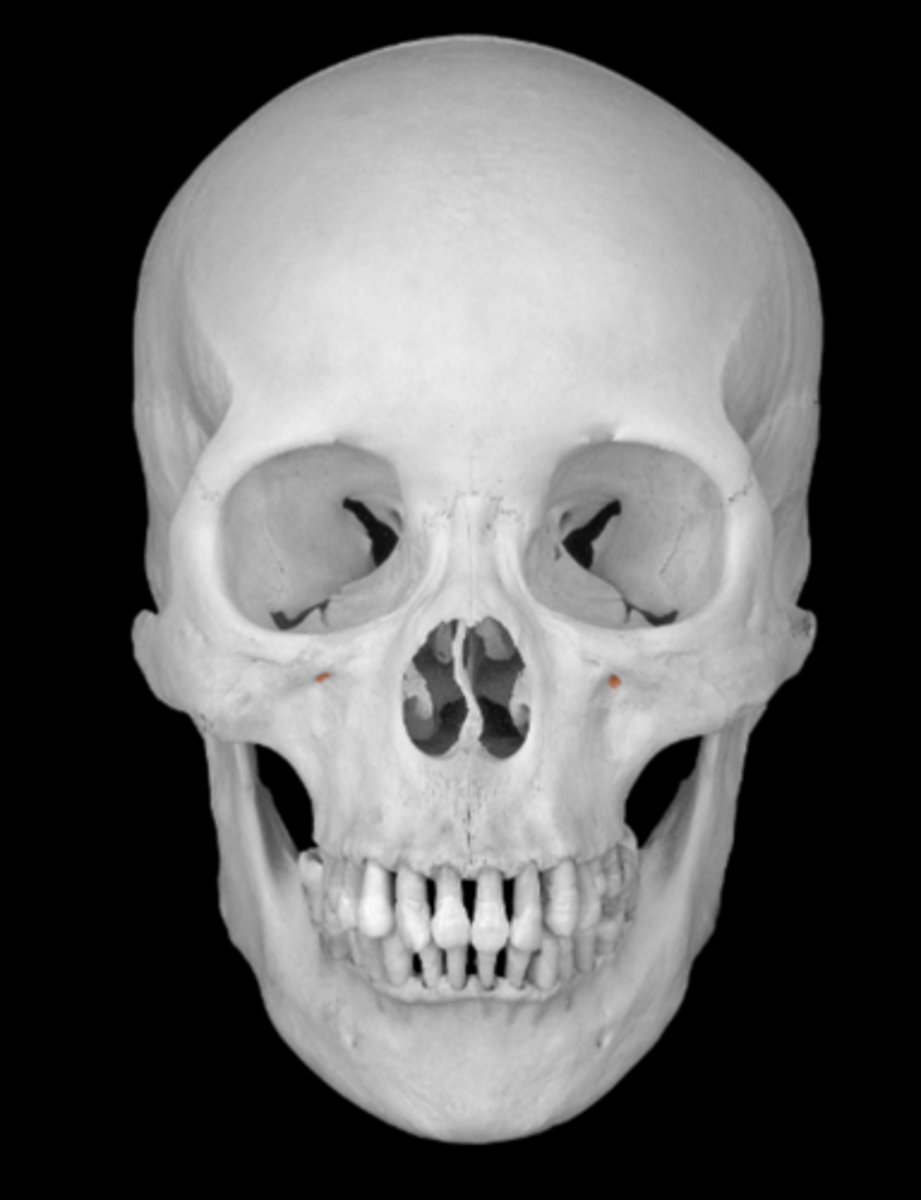

infraorbital foramen of maxilla